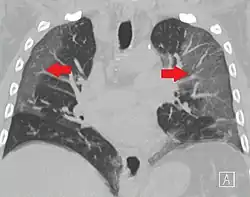

CT image in patient with COVID-19 showing bilateral ground-glass opacities at the periphery of both lungs.

Ground-glass opacity is among the most common imaging findings in patients with confirmed COVID-19.[16][17] One systematic review found that among patients with COVID-19 and abnormal lung findings on CT, greater than 80% had GGOs, with greater than 50% having mixed GGOs and consolidation.[16] GGOs with mixed consolidation has most often been found in elderly populations.[18] Several studies have described a pattern among initial, intermediate, and hospital discharge imaging findings in the disease course of COVID-19. Most commonly, initial CT imaging reveals bilateral GGOs at the periphery of the lungs. During initial stages, this is most often found in the lower lobes, although involvement of the upper lobes and right middle lobe has also been reported early in the disease course.[16][18] This is in contrast to the two similar coronaviruses, SARS and MERS, which more commonly involve only one lung on initial imaging.[19][20] As the COVID-19 infection progresses, GGOs typically become more diffuse and often progress to consolidation.[11][18] This is sometimes accompanied by the development of a crazy paving pattern and interlobular septal thickening.[18] In many cases the most severe pulmonary CT abnormalities occurred within 2 weeks after symptoms began.[17] At this point, many individuals begin showing resolution of consolidation and GGOs as symptoms improve. However, some patients have worsening symptoms and imaging findings, with further increase in septal thickening, GGOs, and consolidation. These patients may develop lung "white-out" with progression to acute respiratory distress syndrome (ARDS) requiring treatment escalation.[17][21]